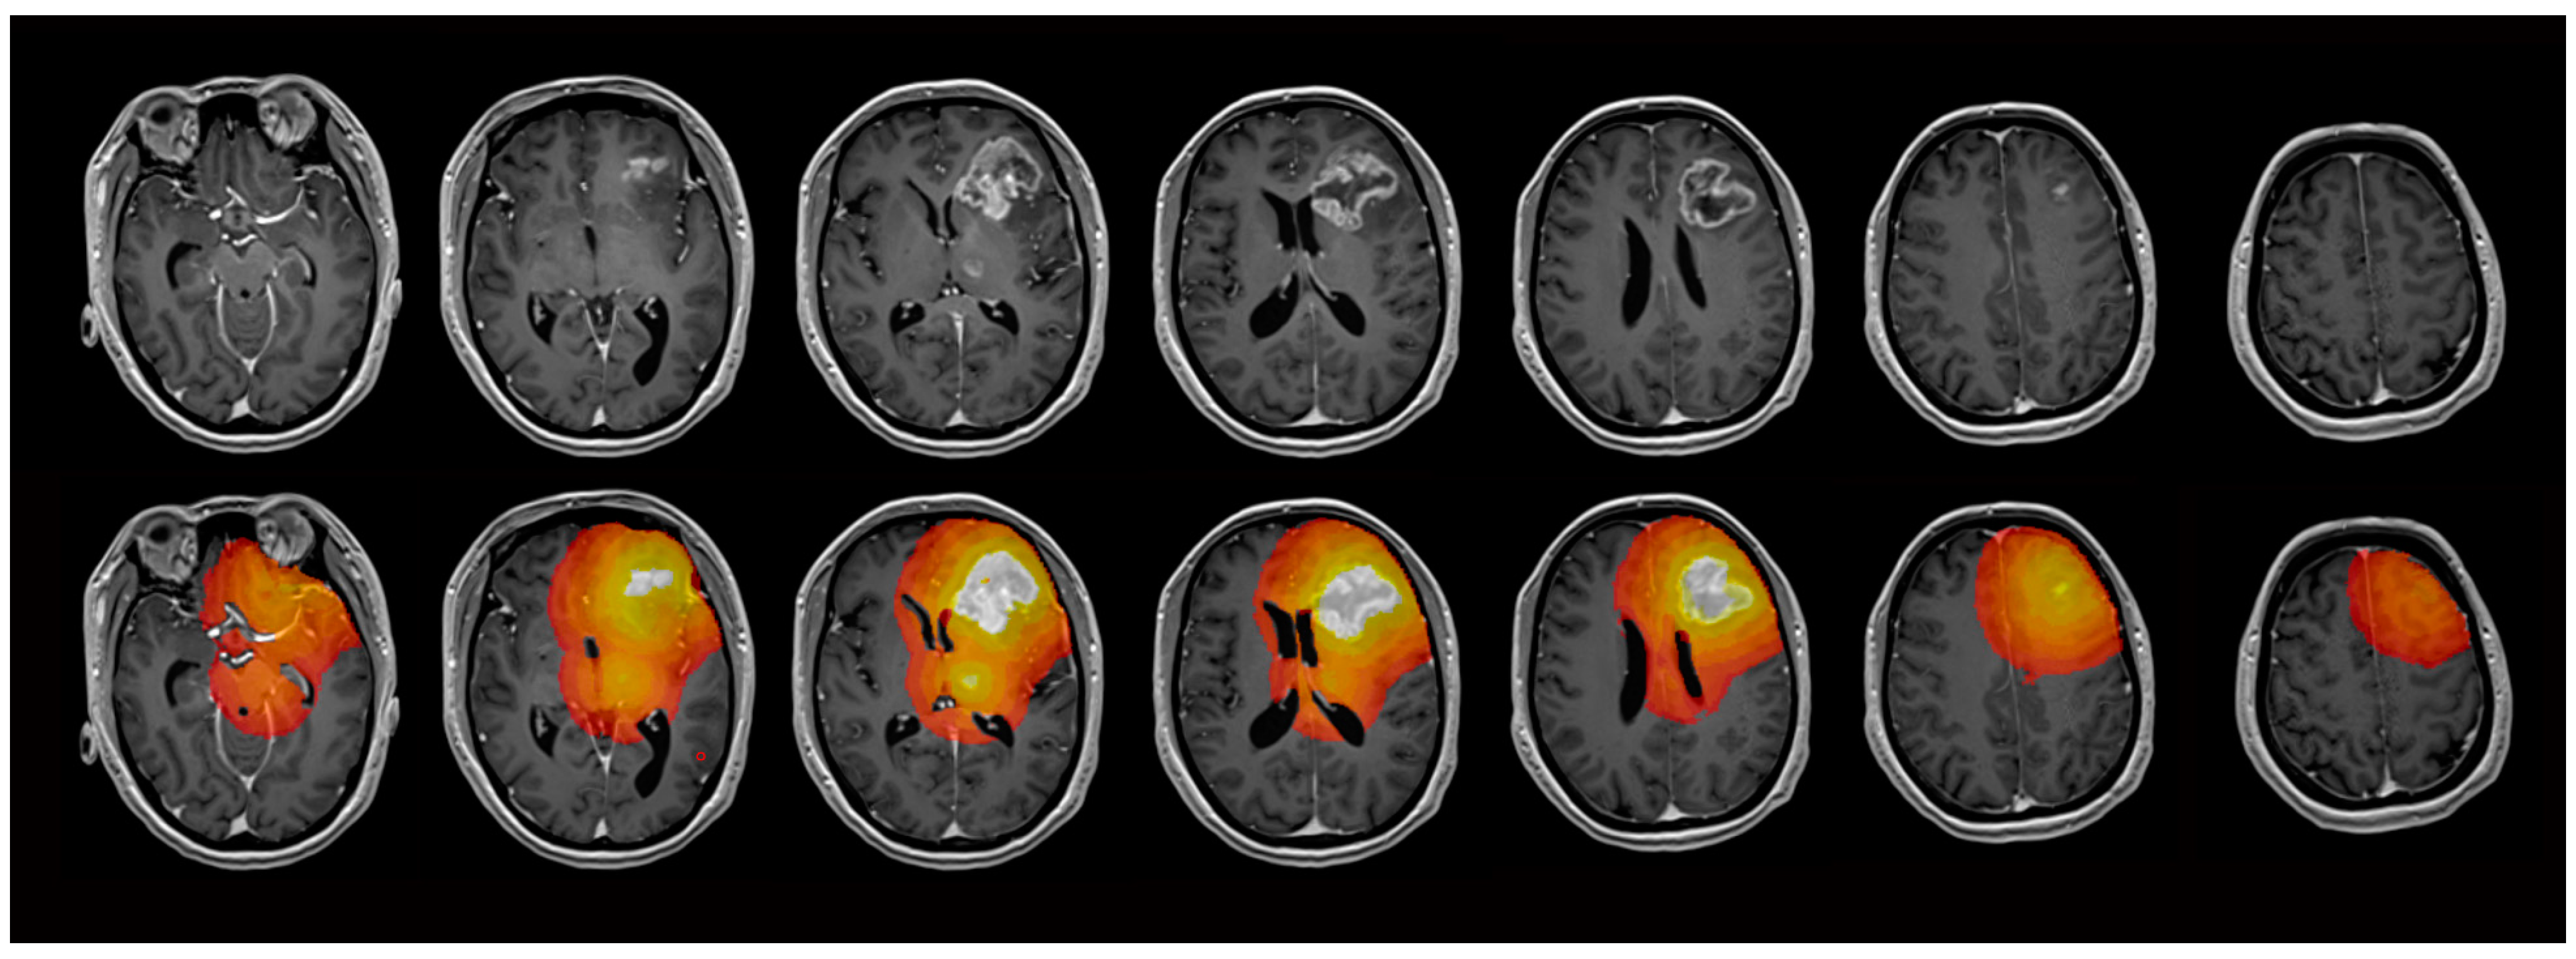

2.4. Image Analysis